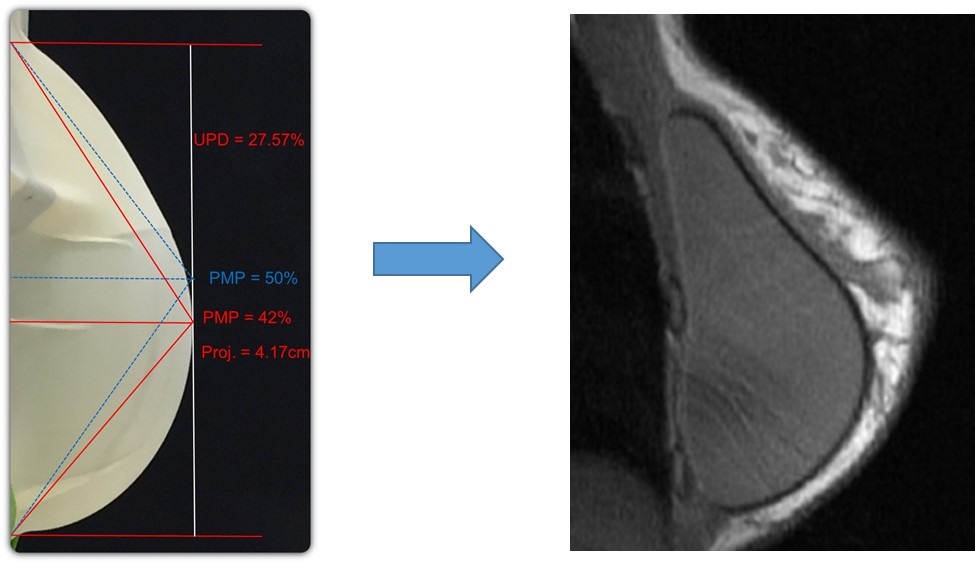

We launched Motiva Implants commercially in October 2010, and to date we have sold approximately 1.4 million units in various countries outside the United States. Motiva Implants incorporate a number of proprietary features that we believe contribute to Motiva Implants’ favorable safety profile as well as a natural appearance and feel. Our latest generation of Motiva Implants utilize our proprietary Ergonomix design, a round base implant that

responds to gravity by shifting its maximum point of projection, offering the projection of a shaped implant without the malpositioning and rotation issues frequently associated with shaped implants. Furthermore, our ProgressiveGel family of silicone gel rheologies consists of four highly purified biocompatible gels with specific visco-elastic properties that we believe enables Motiva Implants to respond to the patient’s motion in ways that more closely mimic the appearance, feel and movement of natural breast tissue. Our catalog includes over 1,000 product variations, with round, oval and anatomical shapes, two different surfaces and volumes ranging from 105cc to 1,050cc, making it a wider range of options than those offered by our major competitors.

In addition to the safety advantages, our ProgressiveGel family provides for movement characteristics that resemble natural breast tissue. Our later generation Ergonomix products further mimic natural tissue, with a maximum point of projection that shifts downward to create a natural human breast shape when a patient is standing. This allows our Motiva Implants to provide the more natural aesthetics of “shaped” or “teardrop” implants without the risk of associated drawbacks such as breast deformation form rotation and unnaturally hard tactile feel. The images below illustrate the implants’ ability to change shape depending on the patient’s positioning.